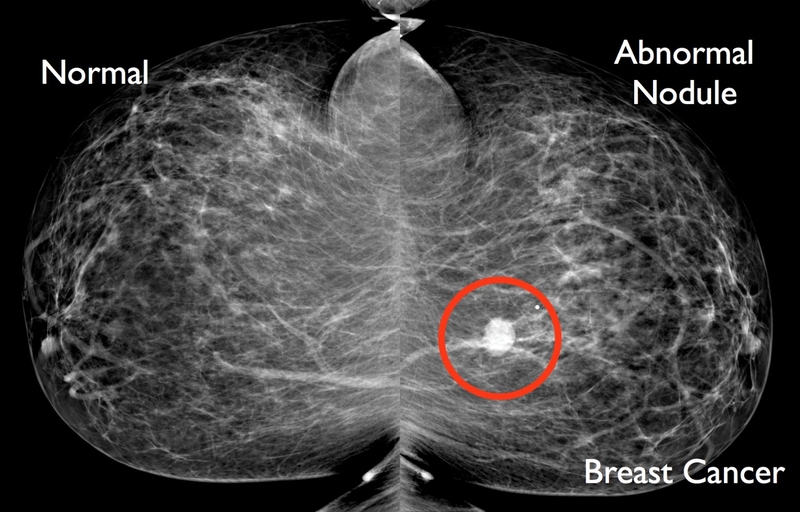

Các xét nghiệm hình ảnh được sử dụng để kiểm tra các bất thường ở vú trước khi chúng được phát hiện (gọi là sàng lọc ung thư vú) hay đánh giá những bất thường đã được xác định, chẳng hạn như khối u vú được phát hiện khi bác sĩ khám.

Các xét nghiệm thường được dùng là: